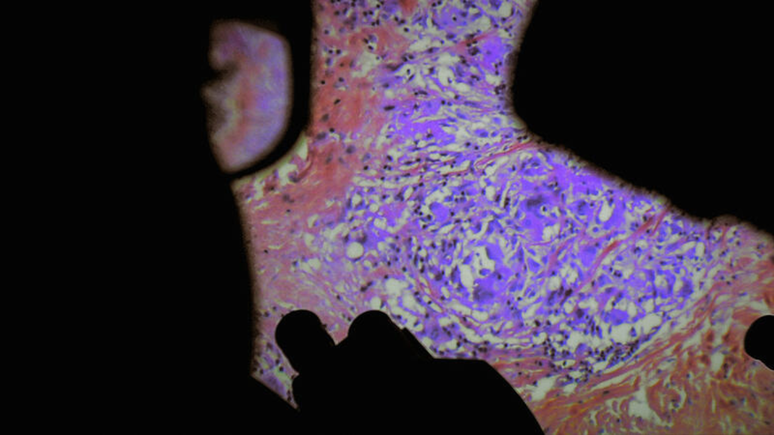

Nenhum filme dos últimos anos confrontou seu público com isso de forma tão implacável quanto De Humani Corporis Fabrica (em tradução livre: A Fábrica do Corpo Humano) - não é um filme de terror, mas sim um documentário! No entanto (ou melhor: exatamente por causa disso), o filme é um verdadeiro teste a nossa coragem.

De Humani Corporis Fabrica é seu mais recente trabalho e nos leva a um lugar onde o "horror corporal" faz parte da vida cotidiana: o hospital.